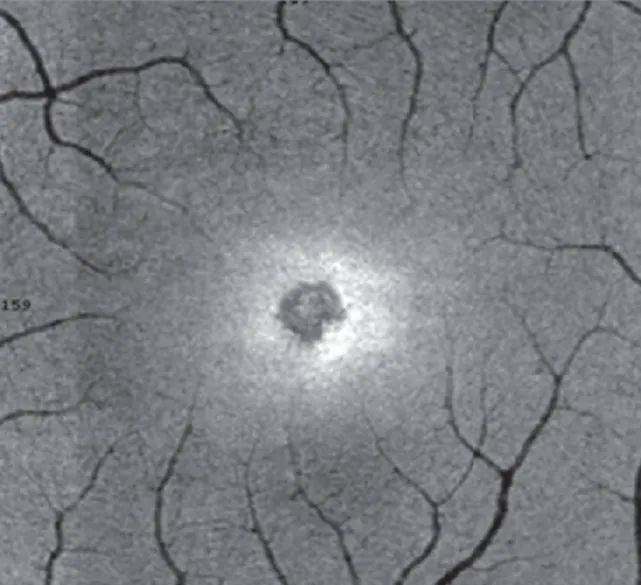

为什么每次在日食预报里都要强调安全观测呢?一定是为了推销巴德膜(绝对不是)。因为每一条安全建议都是来自血的教训。2017年美国日食期间,就有这样一个纽约姑娘的案例——据她本人说,也就看了几秒钟弯月形的太阳,然后就感觉视力模糊,看到的颜色也有些失真。经检查,医生在她左眼的视网膜上找到了一个弯月形的永久性疤痕。所以你看,真的没必要去冒这个险!